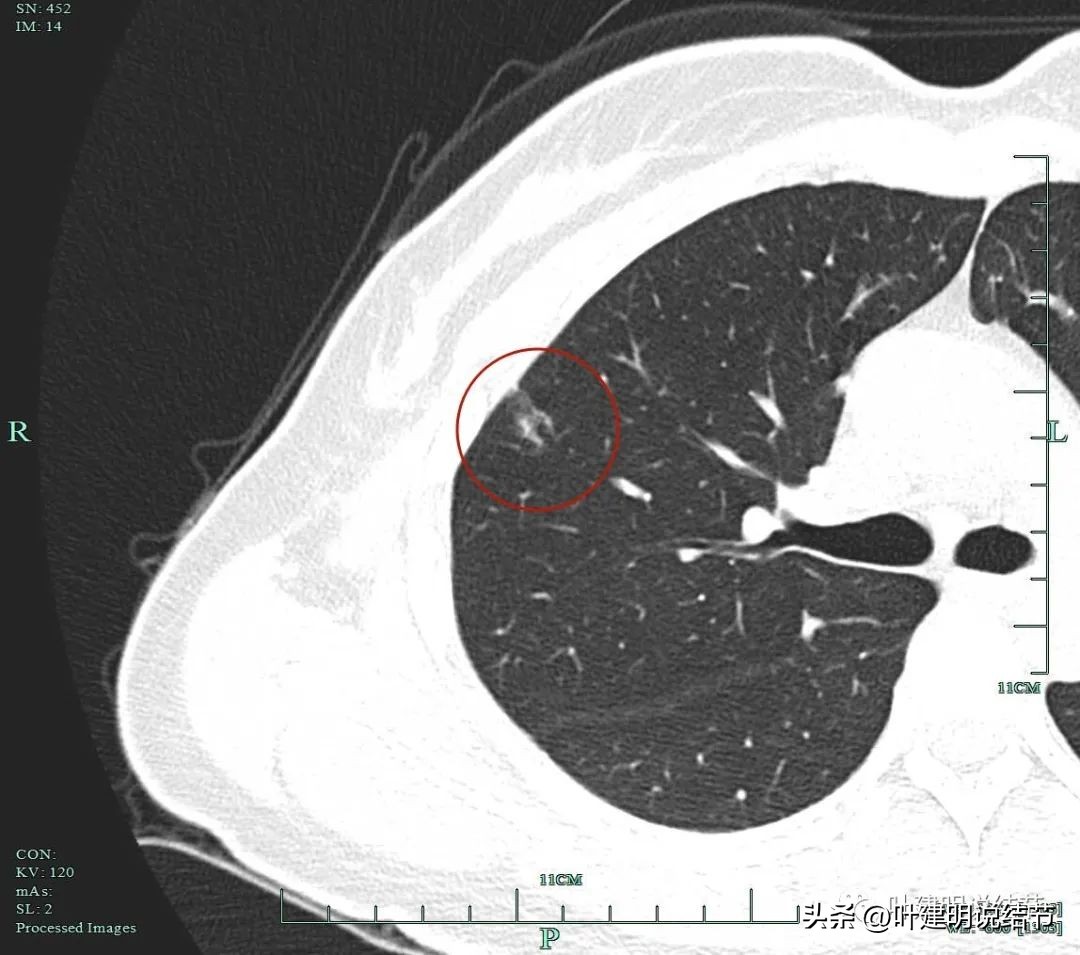

上图示病灶1的定位,红色箭头示病灶1,绿色箭头示定位医用胶。

上两图示病灶2的定位:红色箭头示病灶2,绿色箭头示医用胶。层厚1.25毫米,两者相差5层,也就是说上下相差6.25毫米,术中见到医用胶后,病灶在其下方6.25毫米。